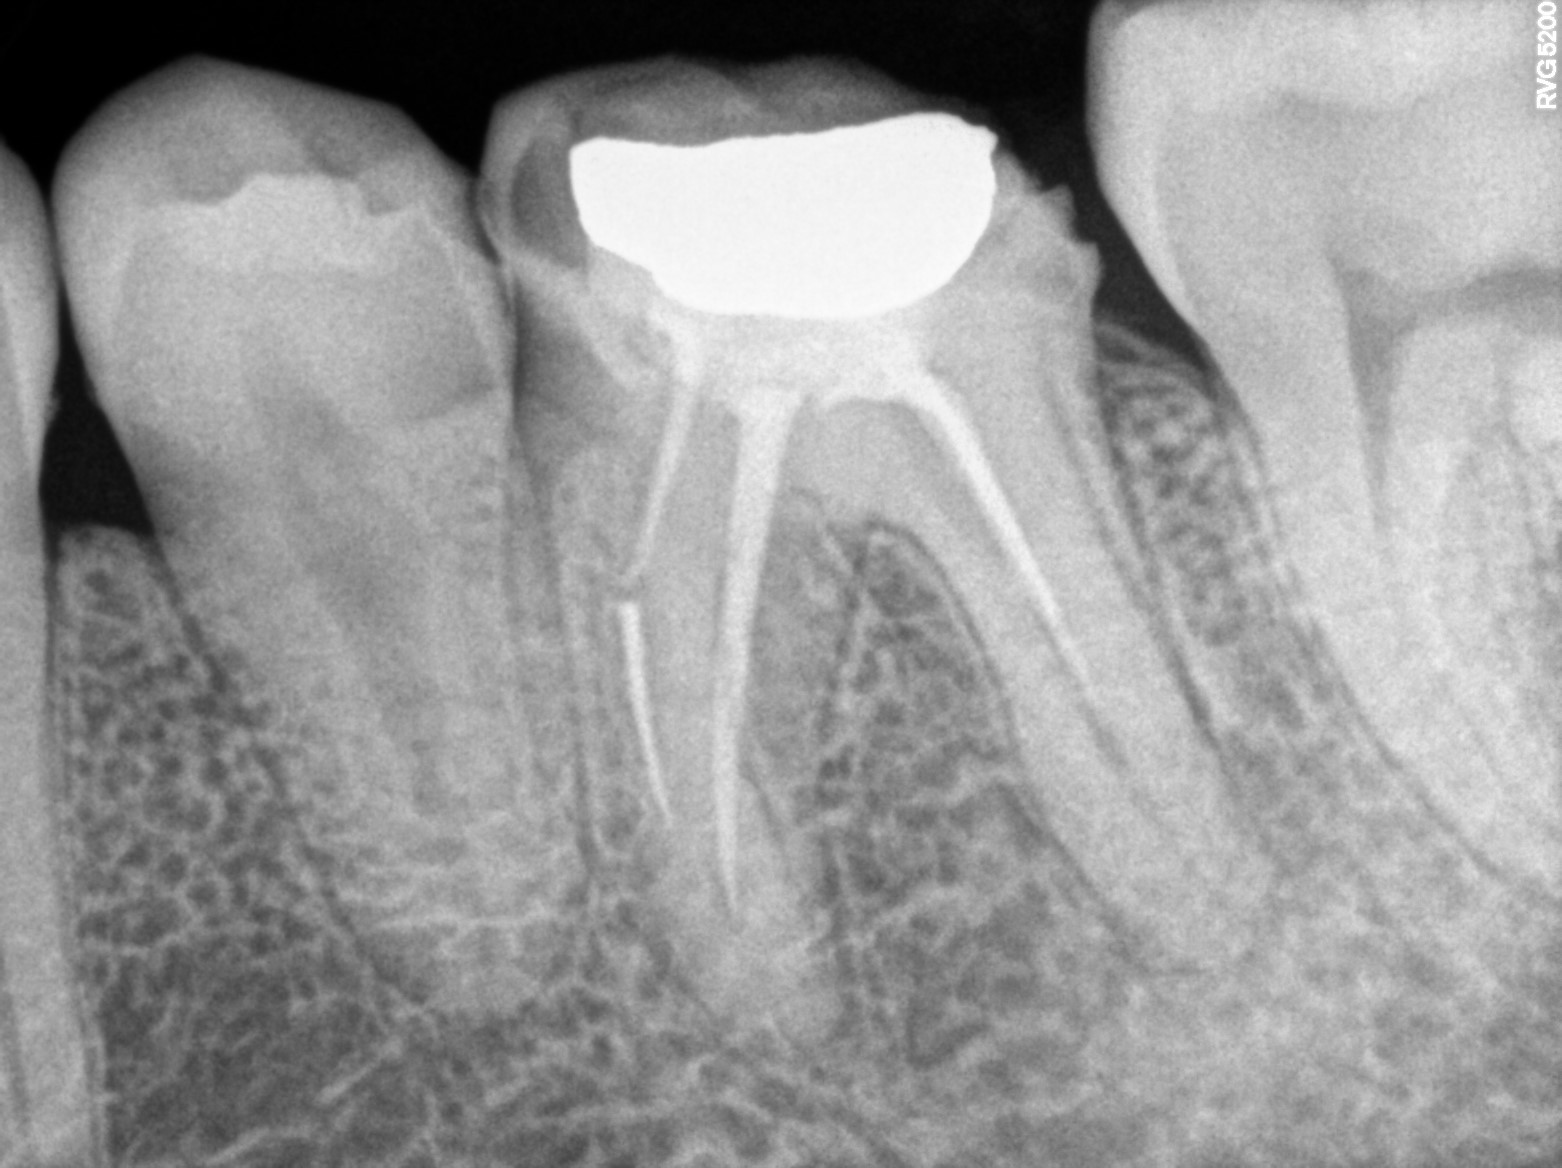

Dental Radiographs FHIR: DocumentReference · LOINC 24641-7

xray_1757778558_1.jpg

24641-7

| Necrosis of dental pulp | K04.1 | 234946006 | resolved | 2026-03-11 | Obturation done with 37 | |

| Root canal treatment | 234780006 | — | ##37 | 2026-03-11 | completed | Obturation done with 37 | |